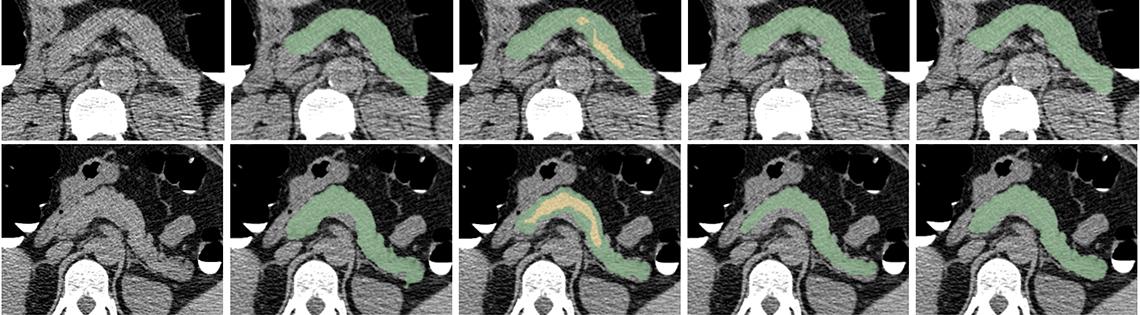

On the Cover

CT scans of the pancreas from two patients (rows). The columns show (from l) the original CT image, a reference manual segmentation, an automated segmentation by use of deep learning, a manual segmentation by a second observer to compute interobserver variability and a repeat manual segmentation to compute intraobserver variability. The automated segmentations were used in a large-scale study of the effect of Type 2 diabetes on the pancreas.

HIMA TALLAM, DANIEL C. ELTON, SUNGWON LEE, PAUL WAKIM, PERRY J. PICKHARDT, RONALD M. SUMMERS